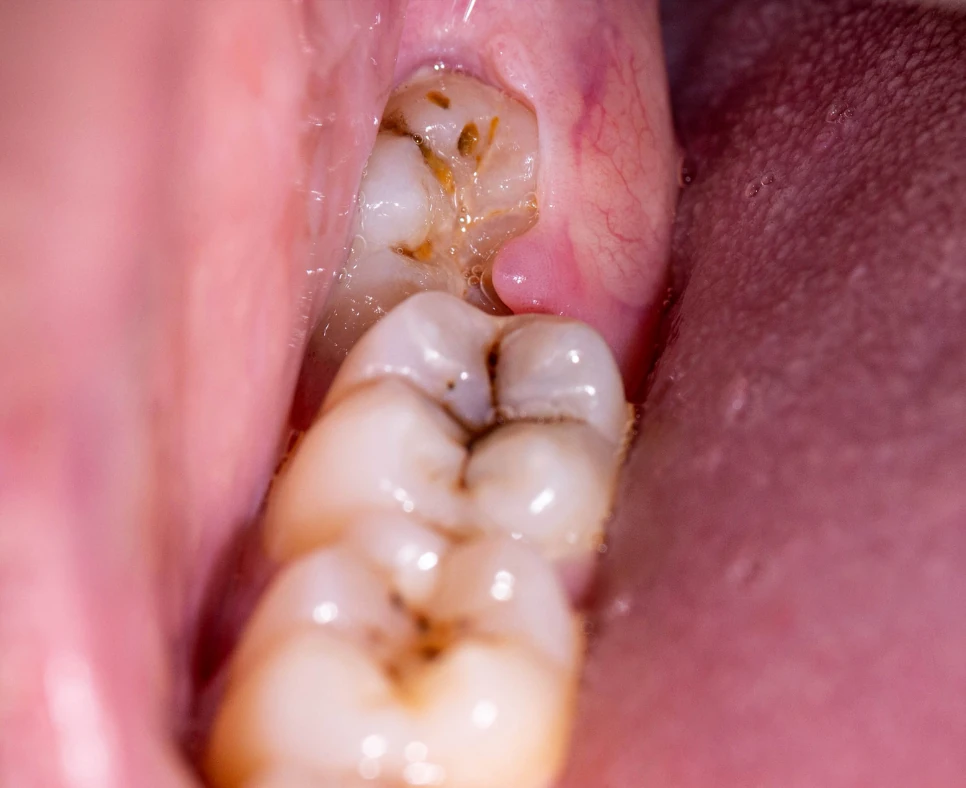

Pericoronitis is characterized by swelling and inflammation of the gum tissue covering a partially erupted tooth, typically a lower wisdom tooth. This common dental condition can cause discomfort, pain, and difficulty opening the mouth. Pericoronitis may also lead to an abscess or infection if left untreated. Acute pericoronitis typically develops rapidly, whereas chronic pericoronitis can persist with recurring episodes. Examining your wisdom teeth regularly and maintaining good oral hygiene can help detect early-stage pericoronitis before it develops into severe symptoms.

- Swollen or inflamed gum tissue near partially erupted teeth

- Impacted or partially erupted wisdom teeth